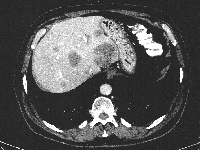

Πρόκειται για ασθενή 75 ετών που διαπιστώθηκε ότι έπασχε από αδενοκαρκίνωμα του σιγμοειδούς με 15 συνολικά ηπατικές μεταστάσεις αμφοτερόπλευρα (εικόνα 1). Η διενέργεια PET-CT δεν ανέδειξε εξωηπατική νόσο. Δεδομένου ότι η πρωτοπαθής εστία τέθηκε υπό προσωρινό έλεγχο με πολυπεκτομή, αποφασίστηκε η αντιμετώπιση πρώτα των μεταστάσεων ("liver first" approach). Με βάση τις εικονικές ηπατεκτομές κατά MEVIS (εικόνα 2) αποφασίστηκε η κάθαρση του ήπατος από το μεταστατικό φορτίο σε δύο στάδια (staged hepatectomy). Ο ασθενής υποβλήθηκε σε 6 κύκλους χημειοθεραπείας (Avastin, FOLFOX). Ακολούθησε δεξιά ηπατεκτομή (εικόνα 3). Κατόπιν υποβλήθηκε σε ακόμα 4 κύκλους χημειοθεραπείας. Η ογκομέτρηση την 4η μετεγχειρητική εβδομάδα ήταν ικανοποιητική (εικόνα 4). Ακολούθησε αριστερή πλάγια ηπατεκτομή (εικόνα 5), η οποία και έφερε την κάθαρση του ηπατικού μεταστατικού φορτίου. Η νέα ογκομέτρηση την 4η μετεγχειρητική εβδομάδα ήταν ξανά ικανοποιητική (εικόνα 6). Συνεχίστηκε η χημειοθεραπεία για ακόμα 4 κύκλους. Ακολούθως, ο ασθενής υποβλήθηκε σε σιγμοειδεκτομή. Τελικά, η χημειοθεραπεία ολοκληρώθηκε με άλλους 6 κύκλους. Ο ασθενής εξακολουθεί να παραμένει ελεύθερος νόσου στους τακτικούς ελέγχους (δις ετησίως) με κολονοσκοπήσεις και CT.